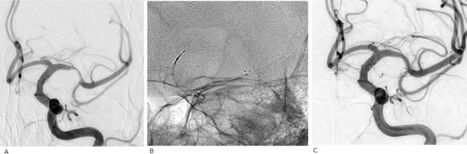

Intracranial atherosclerotic disease (ICAD) significantly contributes to ischemic stroke, especially among Asian populations. Large vessel occlusion (LVO) due to underlying ICAD accounts for 15–35% of acute ischemic stroke cases requiring endovascular therapy. However, the successful recanalization rate of ICAD-related LVO remains lower. The TG dilator is a self-expandable device, temporarily dilating ICAD-related blocked blood vessels.